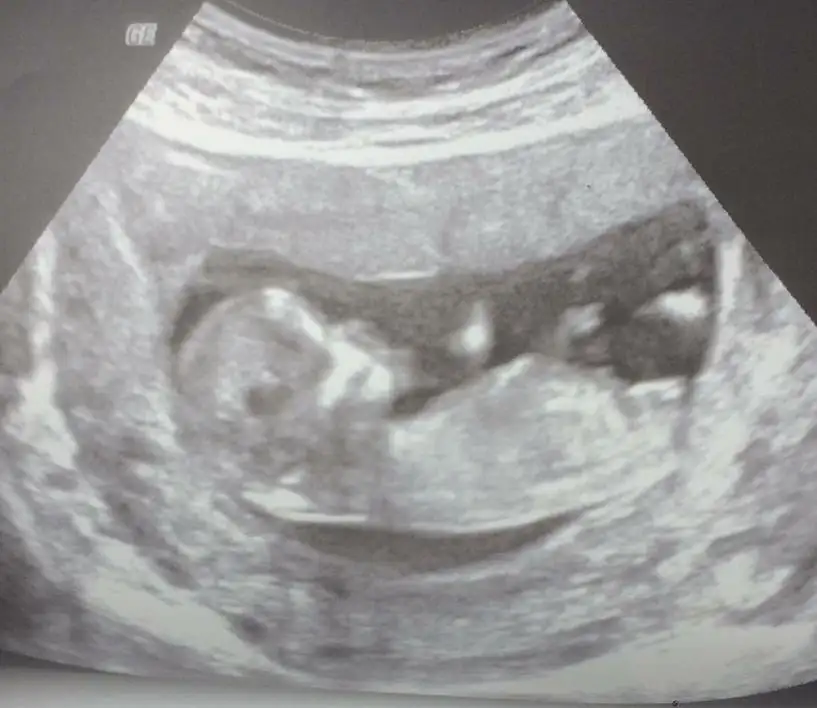

dr soylemeden siz gorun genital nub teorisi ( bebegin cinsiyeti)

Benimkinede bakar mısınız?

10+2yiz ama burda daha dr kontrolumüze var ben çıkıntı falan göremedim kızlar ya yardim edin 😅